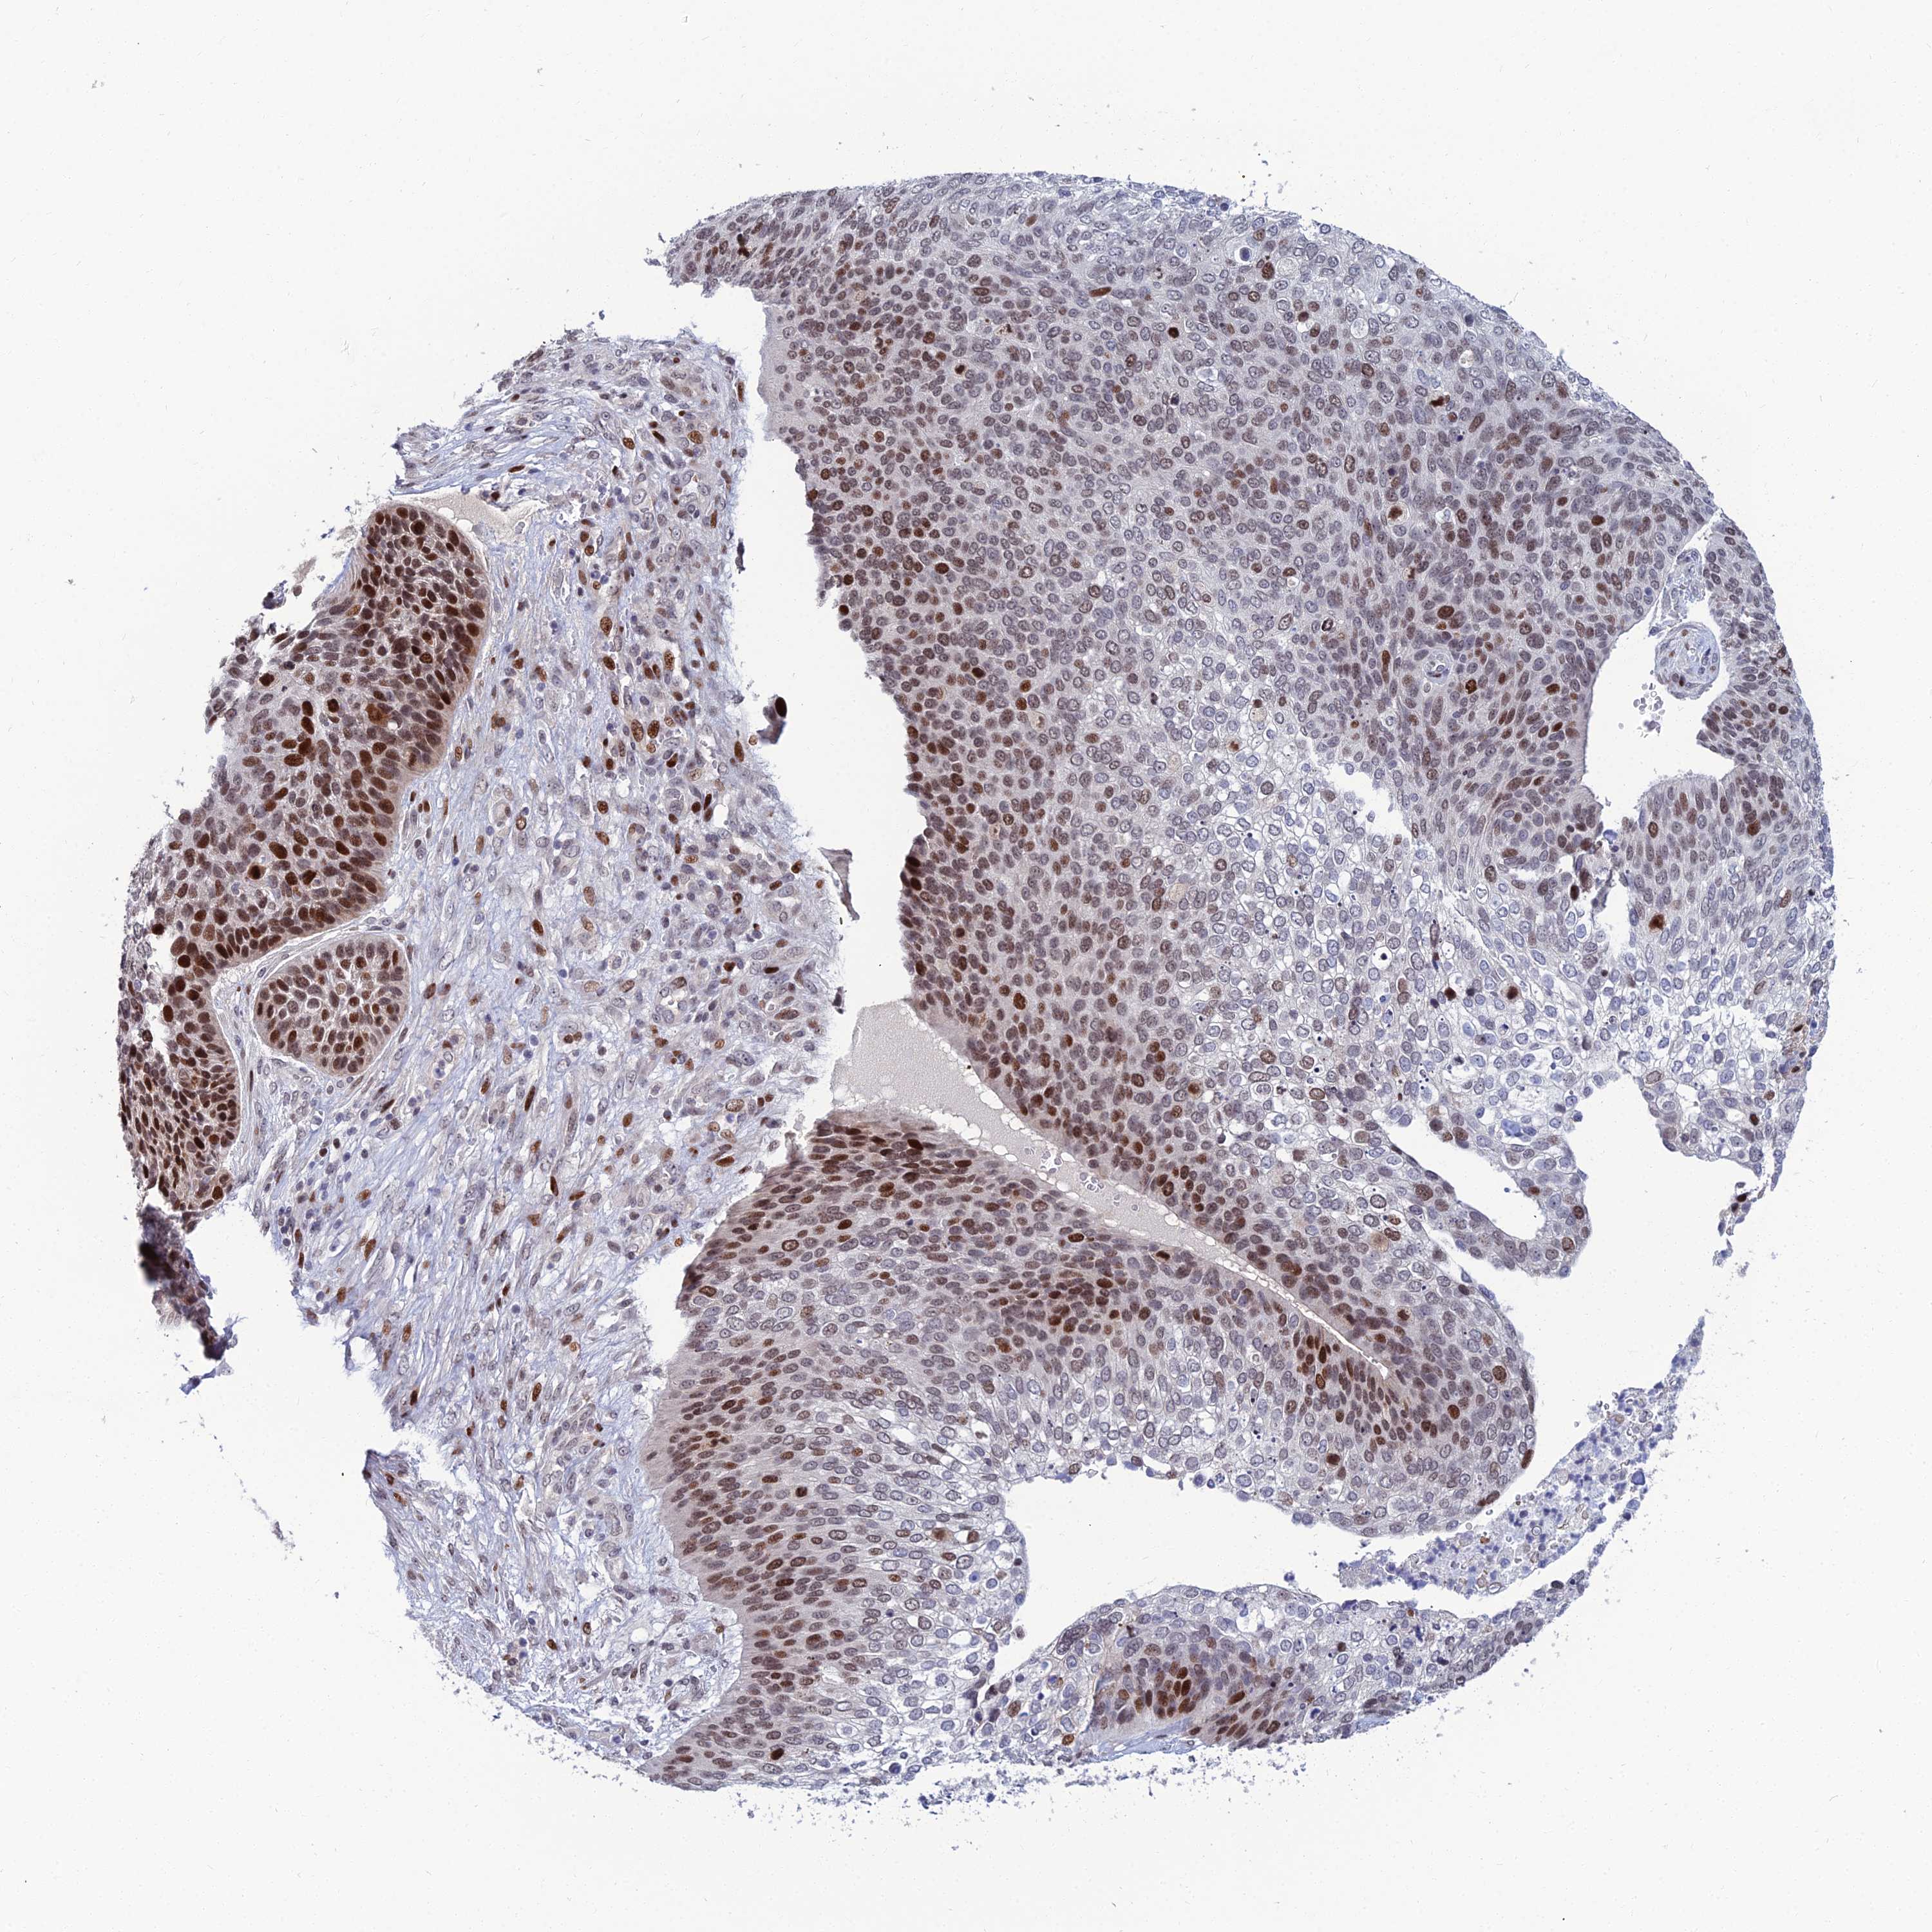

SKIN CANCER - Protein expressioni

A mouse-over function shows sample information and annotation data. Click on an image to view it in a full screen mode. Samples can be filtered based on level of antibody staining by selecting one or several of the following categories: high, medium, low and not detected. The assay and annotation is described here.

Antibody stainingi

Antibody staining in the annotated cell types in the current human tissue is reported as not detected, low, medium, or high, based on conventional immunohistochemistry profiling in selected tissues. This score is based on the combination of the staining intensity and fraction of stained cells.

Each image is clickable and will lead to virtual microscopy that enables deeper exploration of all samples and also displays staining intensity scores, fraction scores and subcellular localization as well as patient and tissue information for each sample.

Antibody HPA045275

Staining

High

Intensity

Strong

Quantity

>75%

Location

Nuclear

Squamous cell carcinoma, metastatic, NOS

Squamous cell carcinoma, NOS